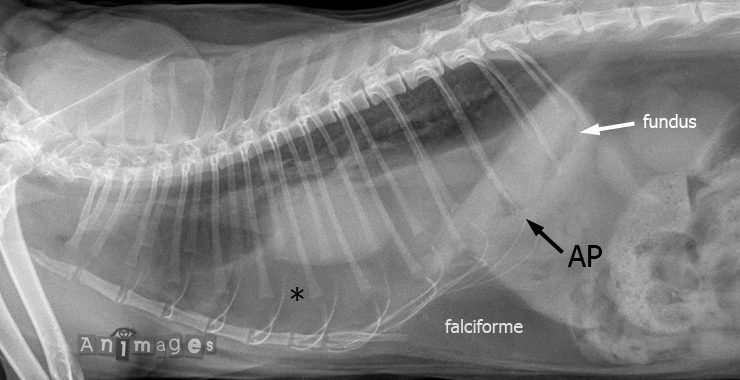

latérale